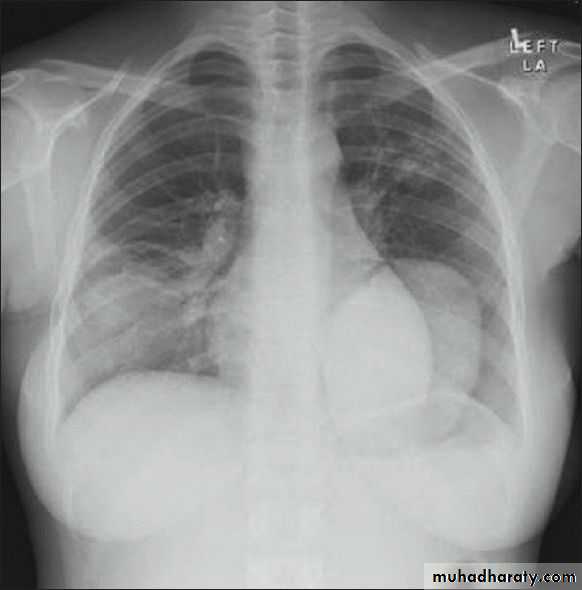

History; too shy to take of his shirt in the pool!